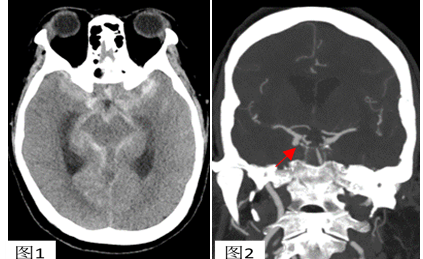

头颅CT显示左侧基底池及侧裂血量较对侧多

头CTA断层可清楚显示右侧后交通段动脉瘤